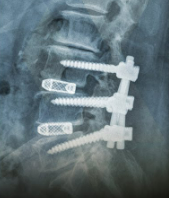

MRI와 X-Ray를 번갈아보며 들은 설명으로는 디스크 2개 터졌고, 협착이 심해서 신경을 너무 눌러 거의 막힌 상태이며, 측만도 있고 해서 뼈 3개 즉 2 마디 유합이 필요하다고 한다.

다행히 양방향 최소 침습법으로 하니, 옆구리로 들어가서 터진 디스크를 빼내고,

인공 대체물 Cage로 교체하고, 등 뒤로 들어가서 나사 6개로 고정을 해야 한다고 한다.

칼로 째는 부위가 적기 때문에 회복이 빠르다는 장점이 있는 방식이다.

유합술.png 나사 6개, Cage 2개. 나의 미래의 모습.

그리고 뼈 3개 고정(나사 6개)부터 국가에서 장애 등급이 나온다. 남은 평생은 장애인으로 등록되어 살아가게 된다. 그만큼 큰 수술이다.